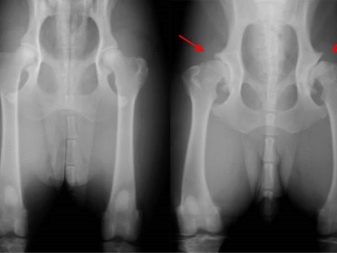

For example, they often have hip dysplasia, diabetes, and hypothyroidism. Among other common ailments that are characteristic of dogs of this breed, problems such as aortic stenosis, melanoma, and cataracts can be noted.